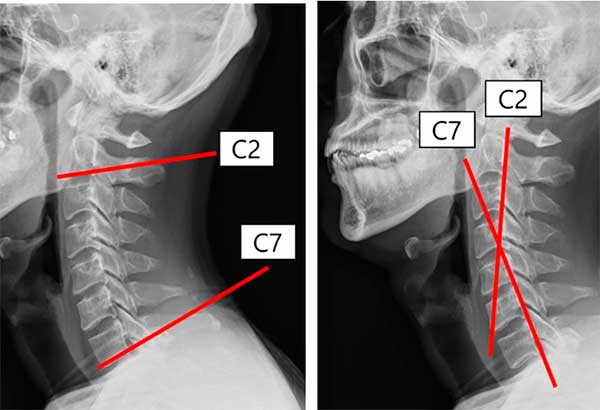

¿Qué almohadas son buenas para la rectificación cervical?

Si tienes rectificación cervical, elegir bien tu almohada es clave. Apuesta por un diseño ergonómico, de espuma viscoelástica, y que se...